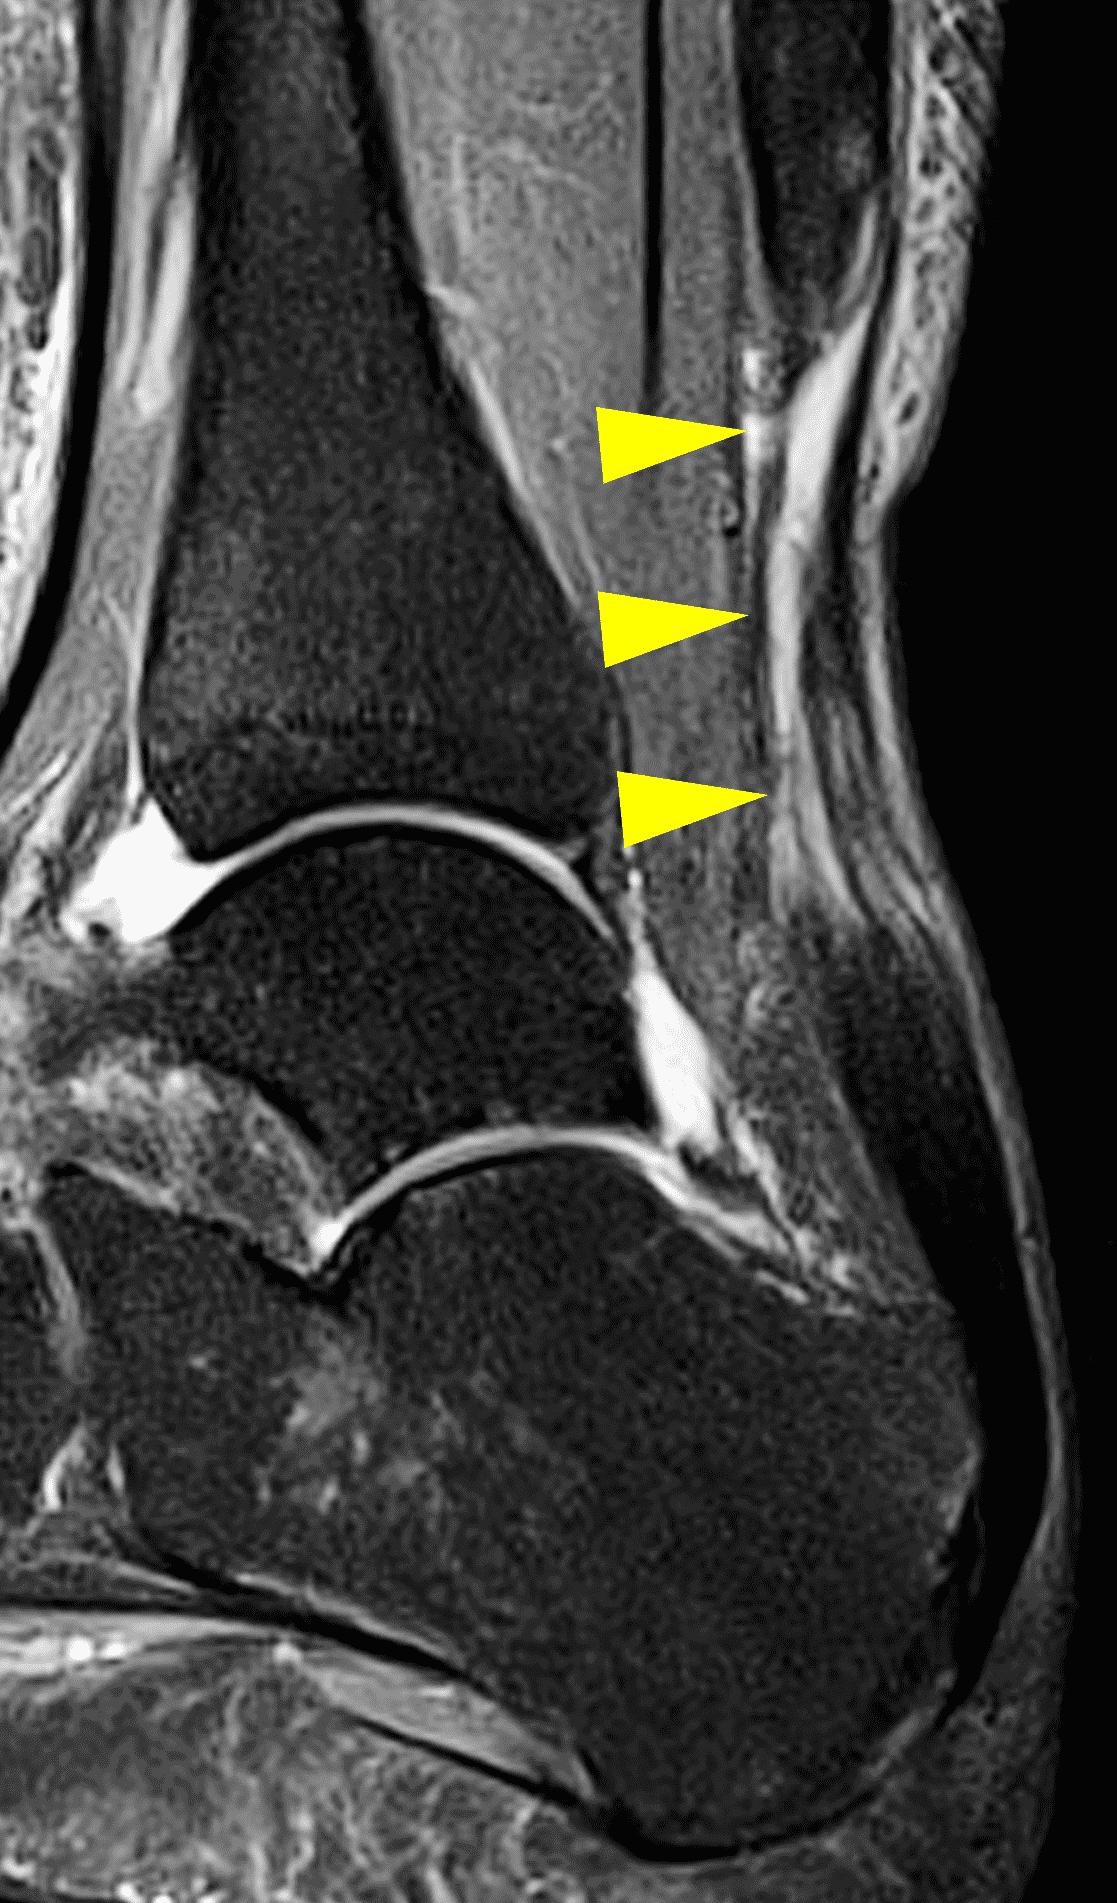

The third important injury location is in the proximal Achilles at the myotendinous junction. While the initial clinical example was at the cranial aspect of the proximal tendon and was amenable to a mini-open or open procedure, tears located at the myotendinous junction are typically treated conservatively except in high-level athletes. A recent meta-analysis confirmed this practice pattern with 67 out 70 cases being treated non-operatively albeit with typical return to function of approximately 80% as assessed by heel rise. The three patients managed surgically were high-level athletes, two of whom returned to full sport and the third who resumed sport at 80% strength.30

In myotendinous tears, it is important to note the size of the gap and the appearance of the myotendinous junction (Figure 11). Recognize that proximal tears may not be completely included in the field-of-view of a standard ankle MR examination. In these cases, it may be necessary to move the coil more proximally and obtain additional images in the distal leg (Figure 12).

Figure 11: Achilles myotendinous junction tear in a 36 year-old. (11A) Sagittal STIR image shows a complete proximal tendon tear at the myotendinous junction with a 2 cm gap (arrow) and moderate diffuse tendinosis in the more distal tendon (arrowheads). (11B) Transverse fat-suppressed fluid-sensitive image also shows edema and degeneration of the myotendinous proximal stump (arrow). Due to the proximal location and extensive underlying tissue degeneration, the patient was not a candidate for surgical repair.